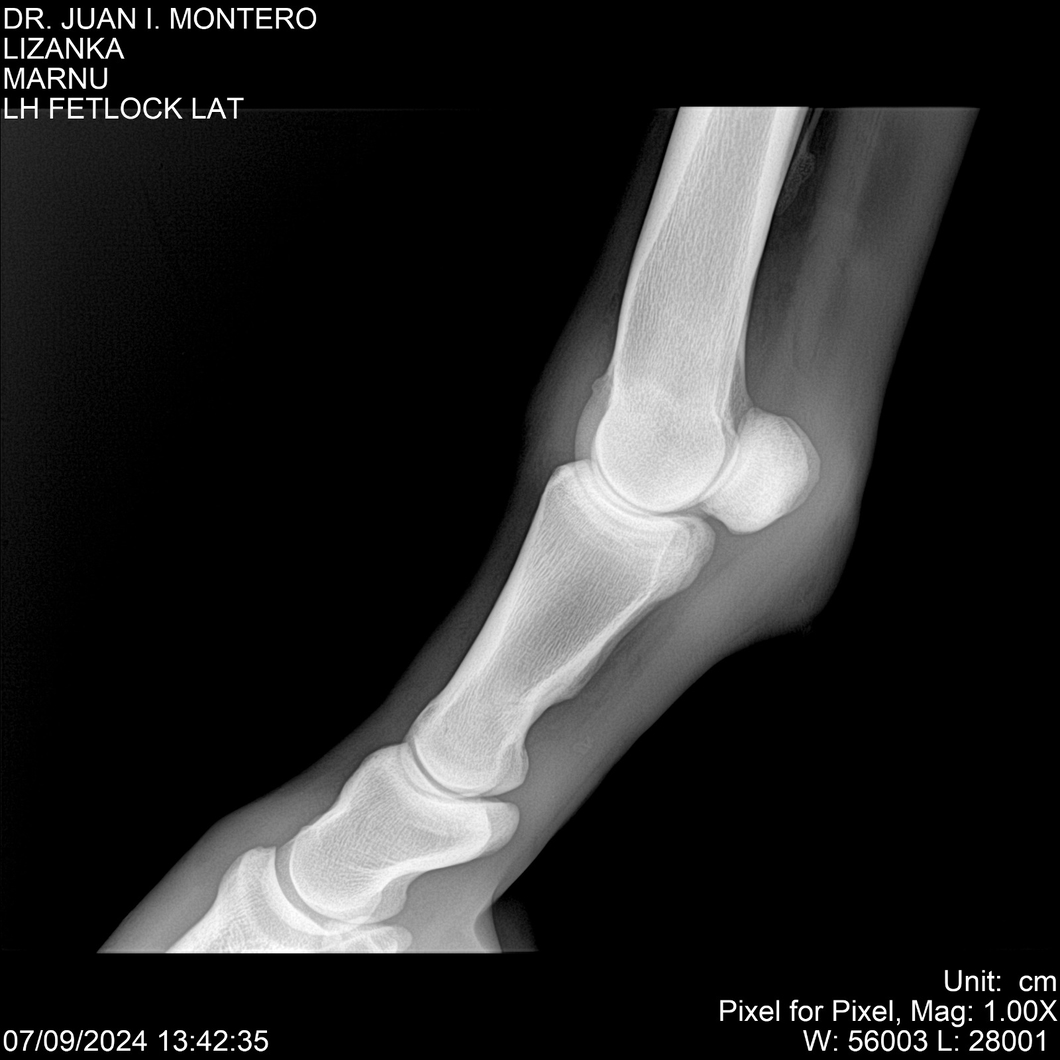

LOTE 18, LIZANKA Lote Anterior Volver al remate Lote Siguiente Ficha Contacto Montevideo - Ficha del Lote Identificador: #282512 Categoría: Yeguarizos Montevideo - 62 Visualizaciones ClicData Contacto Empresa: Abelenda N. R., Walter Hugo Nombre*: Teléfono* : E-mail* : Mensaje Enviar Registrese gratis Este contenido Exclusivo está disponible sólo para usuarios registrados Ingresar